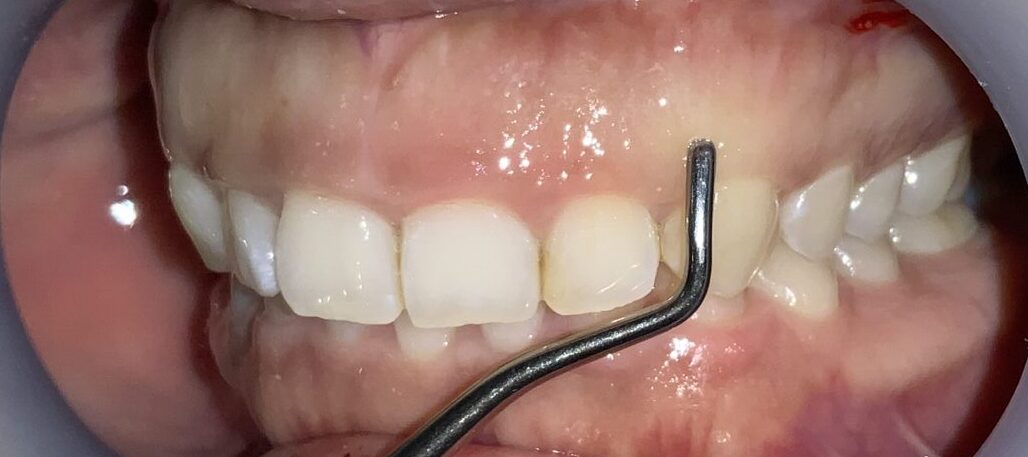

一番気になる、前歯の歯と歯ぐきの位置状態の検査します。

こんなに歯ぐきがかぶさっています。

反対側の歯も調べてみます。前歯の形はとても大切ですから、慎重に検査を進めます。

この歯も同じように、たくさんの歯ぐきが、かぶさっています。